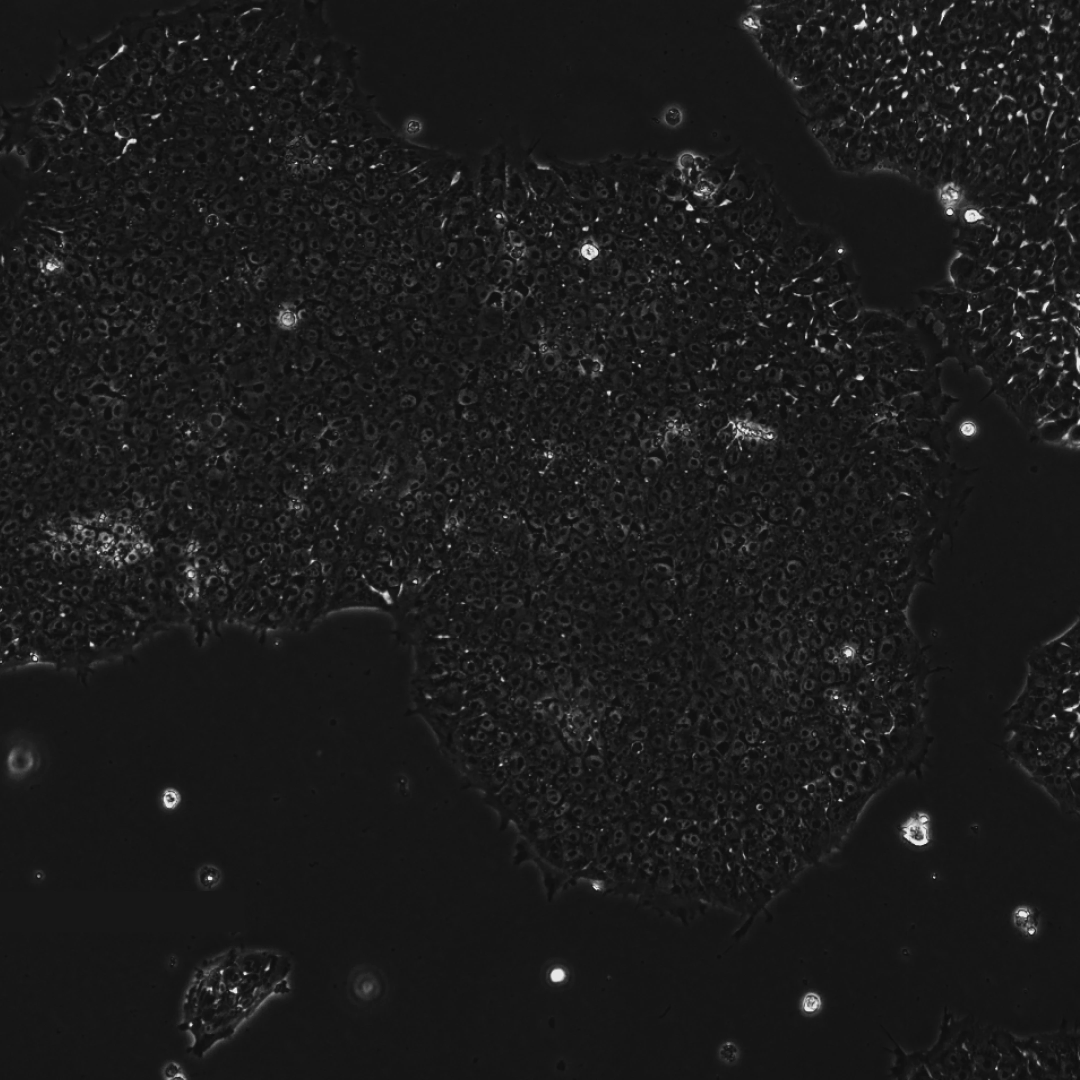

此外,研究团队在第10天通过碱性磷酸酶(AP)染色对RetroSOX和RetroKLF变体进行了验证。

结果显示,形成的细胞集落不仅表达晚期多能性标记物,还表现出强大的AP活性,这是细胞具备多能性的有力标志。

下面三张图中所有的结果共同证实了,研究团队已成功获得健康、且完全重编程的干细胞,从而也全面验证了重编程干细胞的健康与功能。

综上所述,高阳性率、深度的序列编辑、标记物的提前出现以及AP阳性集落的形成,这些早期证据共同表明,AI指导的蛋白质设计能够极大地推动干细胞重编程研究的进程。